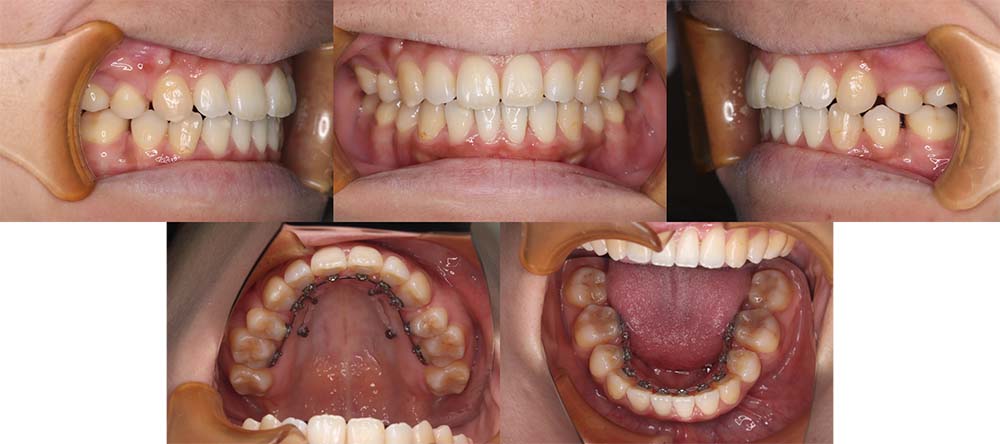

| 症例分類 | 上顎前突、叢生 |

| 診断名 | 上下叢生を伴う骨格性および歯性上顎前突 |

| 主訴 | 歯並びが悪いのが気になる、口元が気になる |

| 年齢 | 19歳5ヶ月 |

| 性別 | 女性 |

| 抜歯部位 | 上の左右第一小臼歯(2本) |

| 使用装置 | 上下裏側のワイヤー装置 |

| 治療期間 | 2年5ヶ月 |

| 保定装置 | 固定式保定装置、取り外し式保定装置(8時間) |

| 費用 |

[検査・診断料] ¥49,500 [基本施術料] ¥1,331,000 [調整料] ¥5,500/回 [抜歯] ¥5,500/本 [保定装置] ¥55,000(税込) 抜歯や虫歯治療は他院にて費用が別途かかります。(抜歯¥4,000〜10,000/本)

上顎前突で上の歯がかなり前にきているため、上顎両側第一小臼歯を抜去して治療を行いました。上の前歯をしっかりと舌側に移動しないといけないため、矯正用アンカースクリューを使用しました。また、下顎はわずかに歯の間の削合(ディスキング)を行い、初診時より歯が前方に出ないように治療を進めました。

口唇閉鎖不全もありましたが、上の前歯が舌側に移動することにより改善することができ、問題なく咬合させることができました。